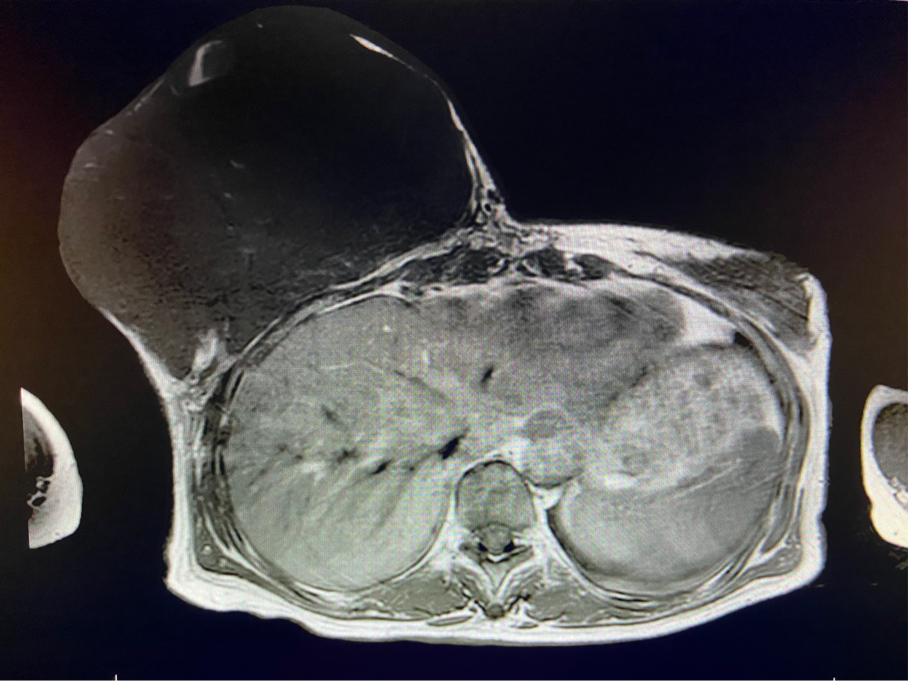

6個(gè)月前,王女士能感覺到右乳腫物明顯增大至“鴨蛋”一般,而且伴有局部皮膚瘙癢及輕度脹痛,可這次王女士并沒有那么幸運(yùn),服藥3個(gè)月不僅沒有控制住腫物,脹痛也越發(fā)嚴(yán)重,超聲檢查提示:右乳囊實(shí)性占位,最大前后徑約10.8cm,右腋窩多發(fā)腫大淋巴結(jié),遂行右乳腫物穿刺活檢術(shù),術(shù)后病理檢查提示:右乳腫物穿刺乳腺組織2條,均可見導(dǎo)管囊性擴(kuò)張,部分區(qū)域間質(zhì)纖維增生,其中1條內(nèi)導(dǎo)管上皮成普通型增生。輾轉(zhuǎn)當(dāng)?shù)囟嗉裔t(yī)院藥物治療后,錢沒有少花,但是療效甚微。

2周前,王女士的右乳外下方皮膚破潰,伴大量滲液,還發(fā)出陣陣惡臭。經(jīng)多方打聽,王女士從外地來到西安國(guó)際醫(yī)學(xué)中心醫(yī)院甲乳外科劉曉敏主任處就診。入院后,迅速完善了一系列相關(guān)術(shù)前檢查:王女士的雙乳外形不對(duì)稱,右乳約22?20cm,皮膚水腫明顯并可見靜脈曲張。右乳外下象限皮膚可見局部破潰,創(chuàng)面有3處,共約6?4cm大小,創(chuàng)面呈暗紅色,伴有血性滲出及惡臭,局部皮膚溫度升高。右側(cè)腋窩可觸及腫大淋巴結(jié)。

該患者右乳巨大腫物術(shù)前初步考慮乳腺葉狀腫瘤可能,因腫瘤太大,幾乎遍及整個(gè)右側(cè)乳房,為保證“無瘤原則”,術(shù)中切除范圍位置未知,極有可能出現(xiàn)皮瓣缺損。于是,經(jīng)過和整形醫(yī)院郭樹忠院長(zhǎng)、整形外科王愛武主任的討論,提供了兩種手術(shù)方式,一是創(chuàng)面修復(fù)(植皮或轉(zhuǎn)移皮瓣修復(fù)創(chuàng)面),二是乳房再造,與患者及家屬溝通后,決定先解決腫物,3年病情不再?gòu)?fù)發(fā)后,可以再考慮乳房重建。